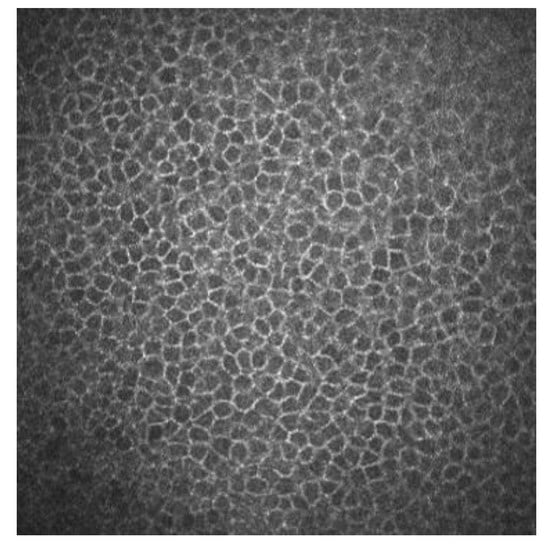

Superficial epithelial cells are 20–30 μm long and about 5 μm wide. They are observed as polygonal cells of different sizes and reflectivity with the confocal microscopy. They show a visible nucleus surrounded by a dark band. Winged cells are also observed, and show lower reflectivity. They also show variations in size and have bright borders and nuclei but do not show the dark ring that the superficial epithelial cells’ nuclei have [3,4]. Basal epithelial cells have a 10–15 μm diameter. They form a regular mosaic with dark cell bodies and bright borders (Figure 1) [3,5].

Figure 1.

Basal epithelial cells of a human cornea observed with the corneal confocal microscopy HRT II.